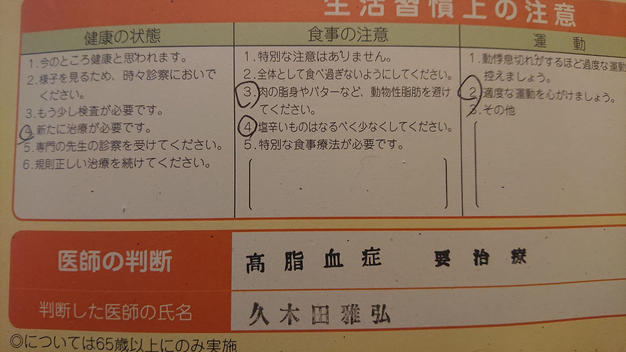

健康第一♪

June 11,2019|Satoshiこんにちはー! トラウムスクーバのサトシです(^^♪ 季節の変わり目は、体調崩しやすいので皆さん気を付けてくださいねー。 私もなんか体が重たい・・・。(;^_^A 本日は先月の健診結果を聞きに病院へ。 結果は・・・要治療